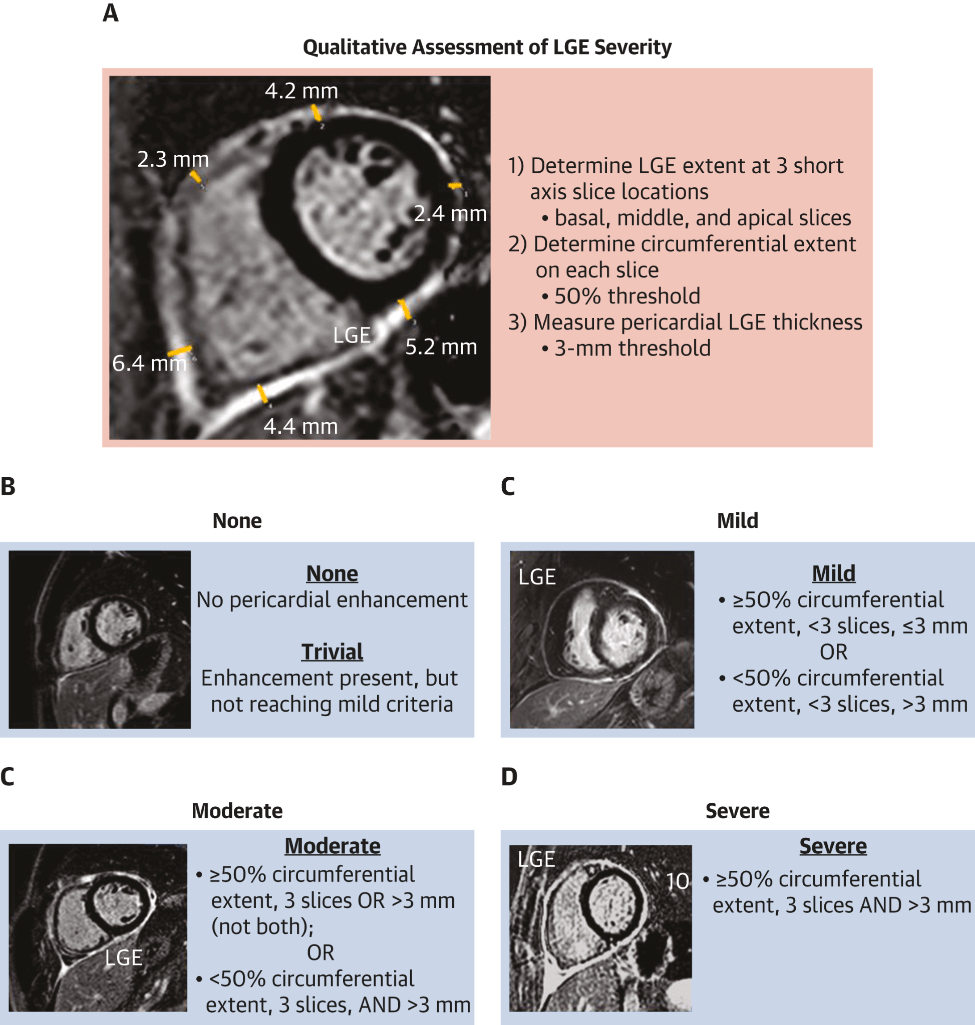

What finding on cardiac MR is primarily used to establish a diagnosis of pericarditis and grade it's severity?

Late gadolinium enhancement/edema - on phase-sensitivity inversion recovery sequence (ideally fat-suppressed), indicating neovascularization or inflammation